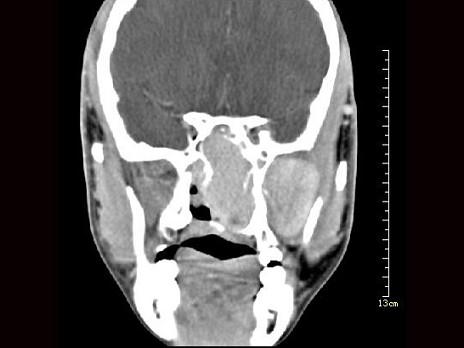

问题 男性,19岁,左侧鼻腔反复出血1年余,CT、MRI扫描如图所示,请选择最可能诊断()

选项 A.鼻息肉 B.鼻咽腔脓肿 C.鼻咽部青年纤维血管瘤 D.鼻咽癌 E.鼻咽部淋巴瘤

答案 C